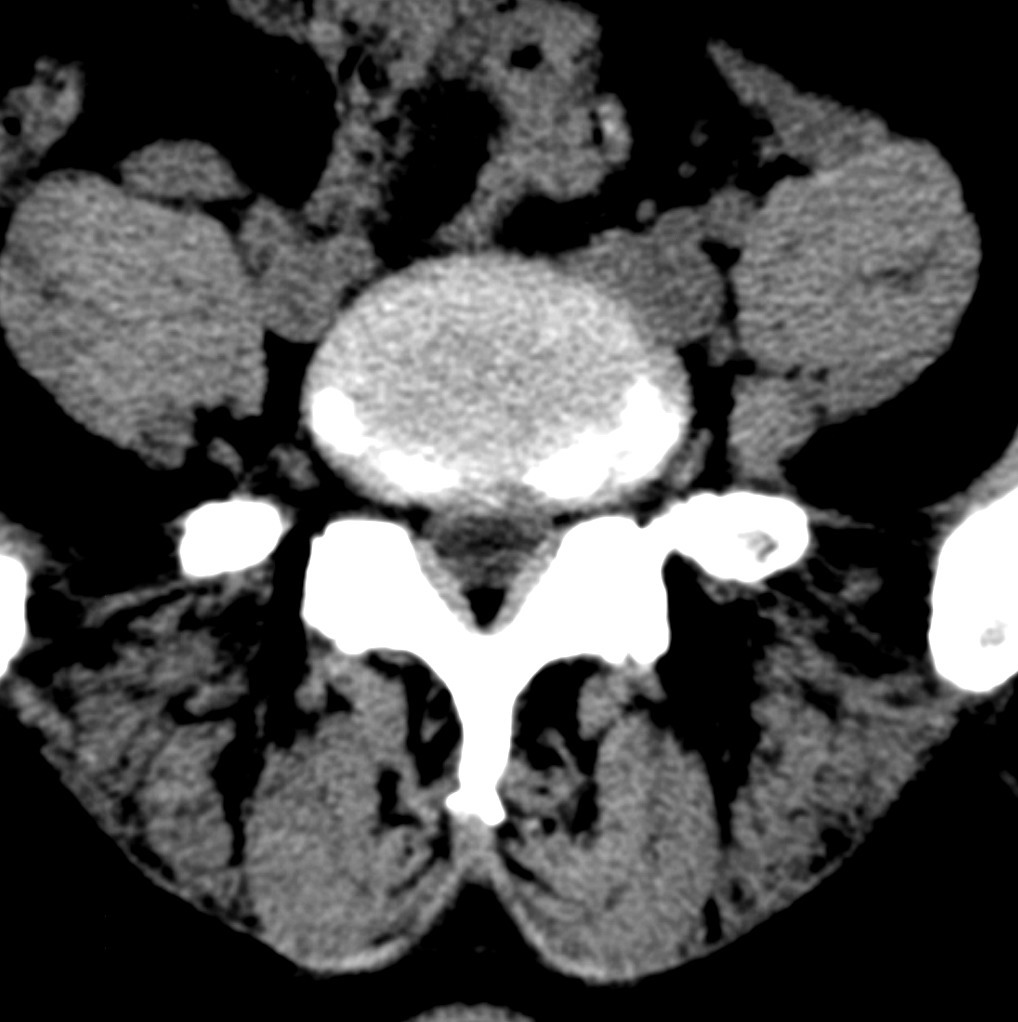

标题: CT19570:是否为腰脱? [打印本页]

标题: CT19570:是否为腰脱?

可以定腰脱否?

大于椎体的环状软组织影,椎间盘膨出

椎间盘膨出伴突出

支持间盘膨出伴突出。

双边征,考虑滑脱。

椎间盘突出

腰脱证据不足。

椎间盘膨出伴突出!

椎间盘突出,

椎间盘改变并不是很明显,黄韧带似乎有肥厚,